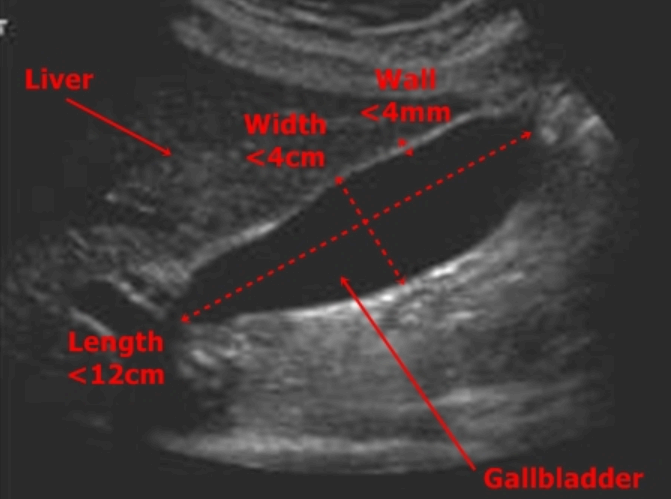

담낭 해부학 (GB anatomy ) 담낭은 길이는 7~10cm, 폭 3~5cm으로 간과 함께 복막에 싸여 있으며 간우측하면 담낭와에 고정되어 있다. 담낭은 저부(fundus), 체부(body), 경부(neck)로 구분된다. 담낭의 저부는 복측에 있고 경부는 배 측에 있다. 담낭의 저부는 담낭암의 호발부위이고 담낭의 체부는 저부와 경부 사이에 있으며 경부는 담낭관으로 연결되는 부분으로 누두부(hartman pouch)가 있다. 담낭관(cystic duct)은 약 2~4cm이고 내강에 heister valve 가 있어 담즙의 역류를 방지한다. 담낭벽은 매우 얇은 벽을 갖는 주머니로 점막층, 점막하층, 근육층, 장막층으로 구성되며 식전에는 2mm 이하 식후에는 3mm 이하의 두께를 갖는다.

- 담낭벽의 두께 (금식상태) : 2mm 이하

- 담낭벽의 두께 (식후상태): 3mm 이하 / 4mm 이상이면 비정상

- GB wall 밝고 균일한 에코

- GB 내강은 anechoic (무에코)